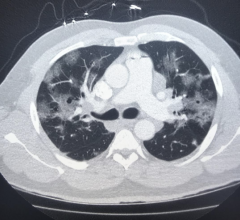

This video shows a computed tomography (CT) scroll through showing bowel ischemia and perforation (see arrows) due to …